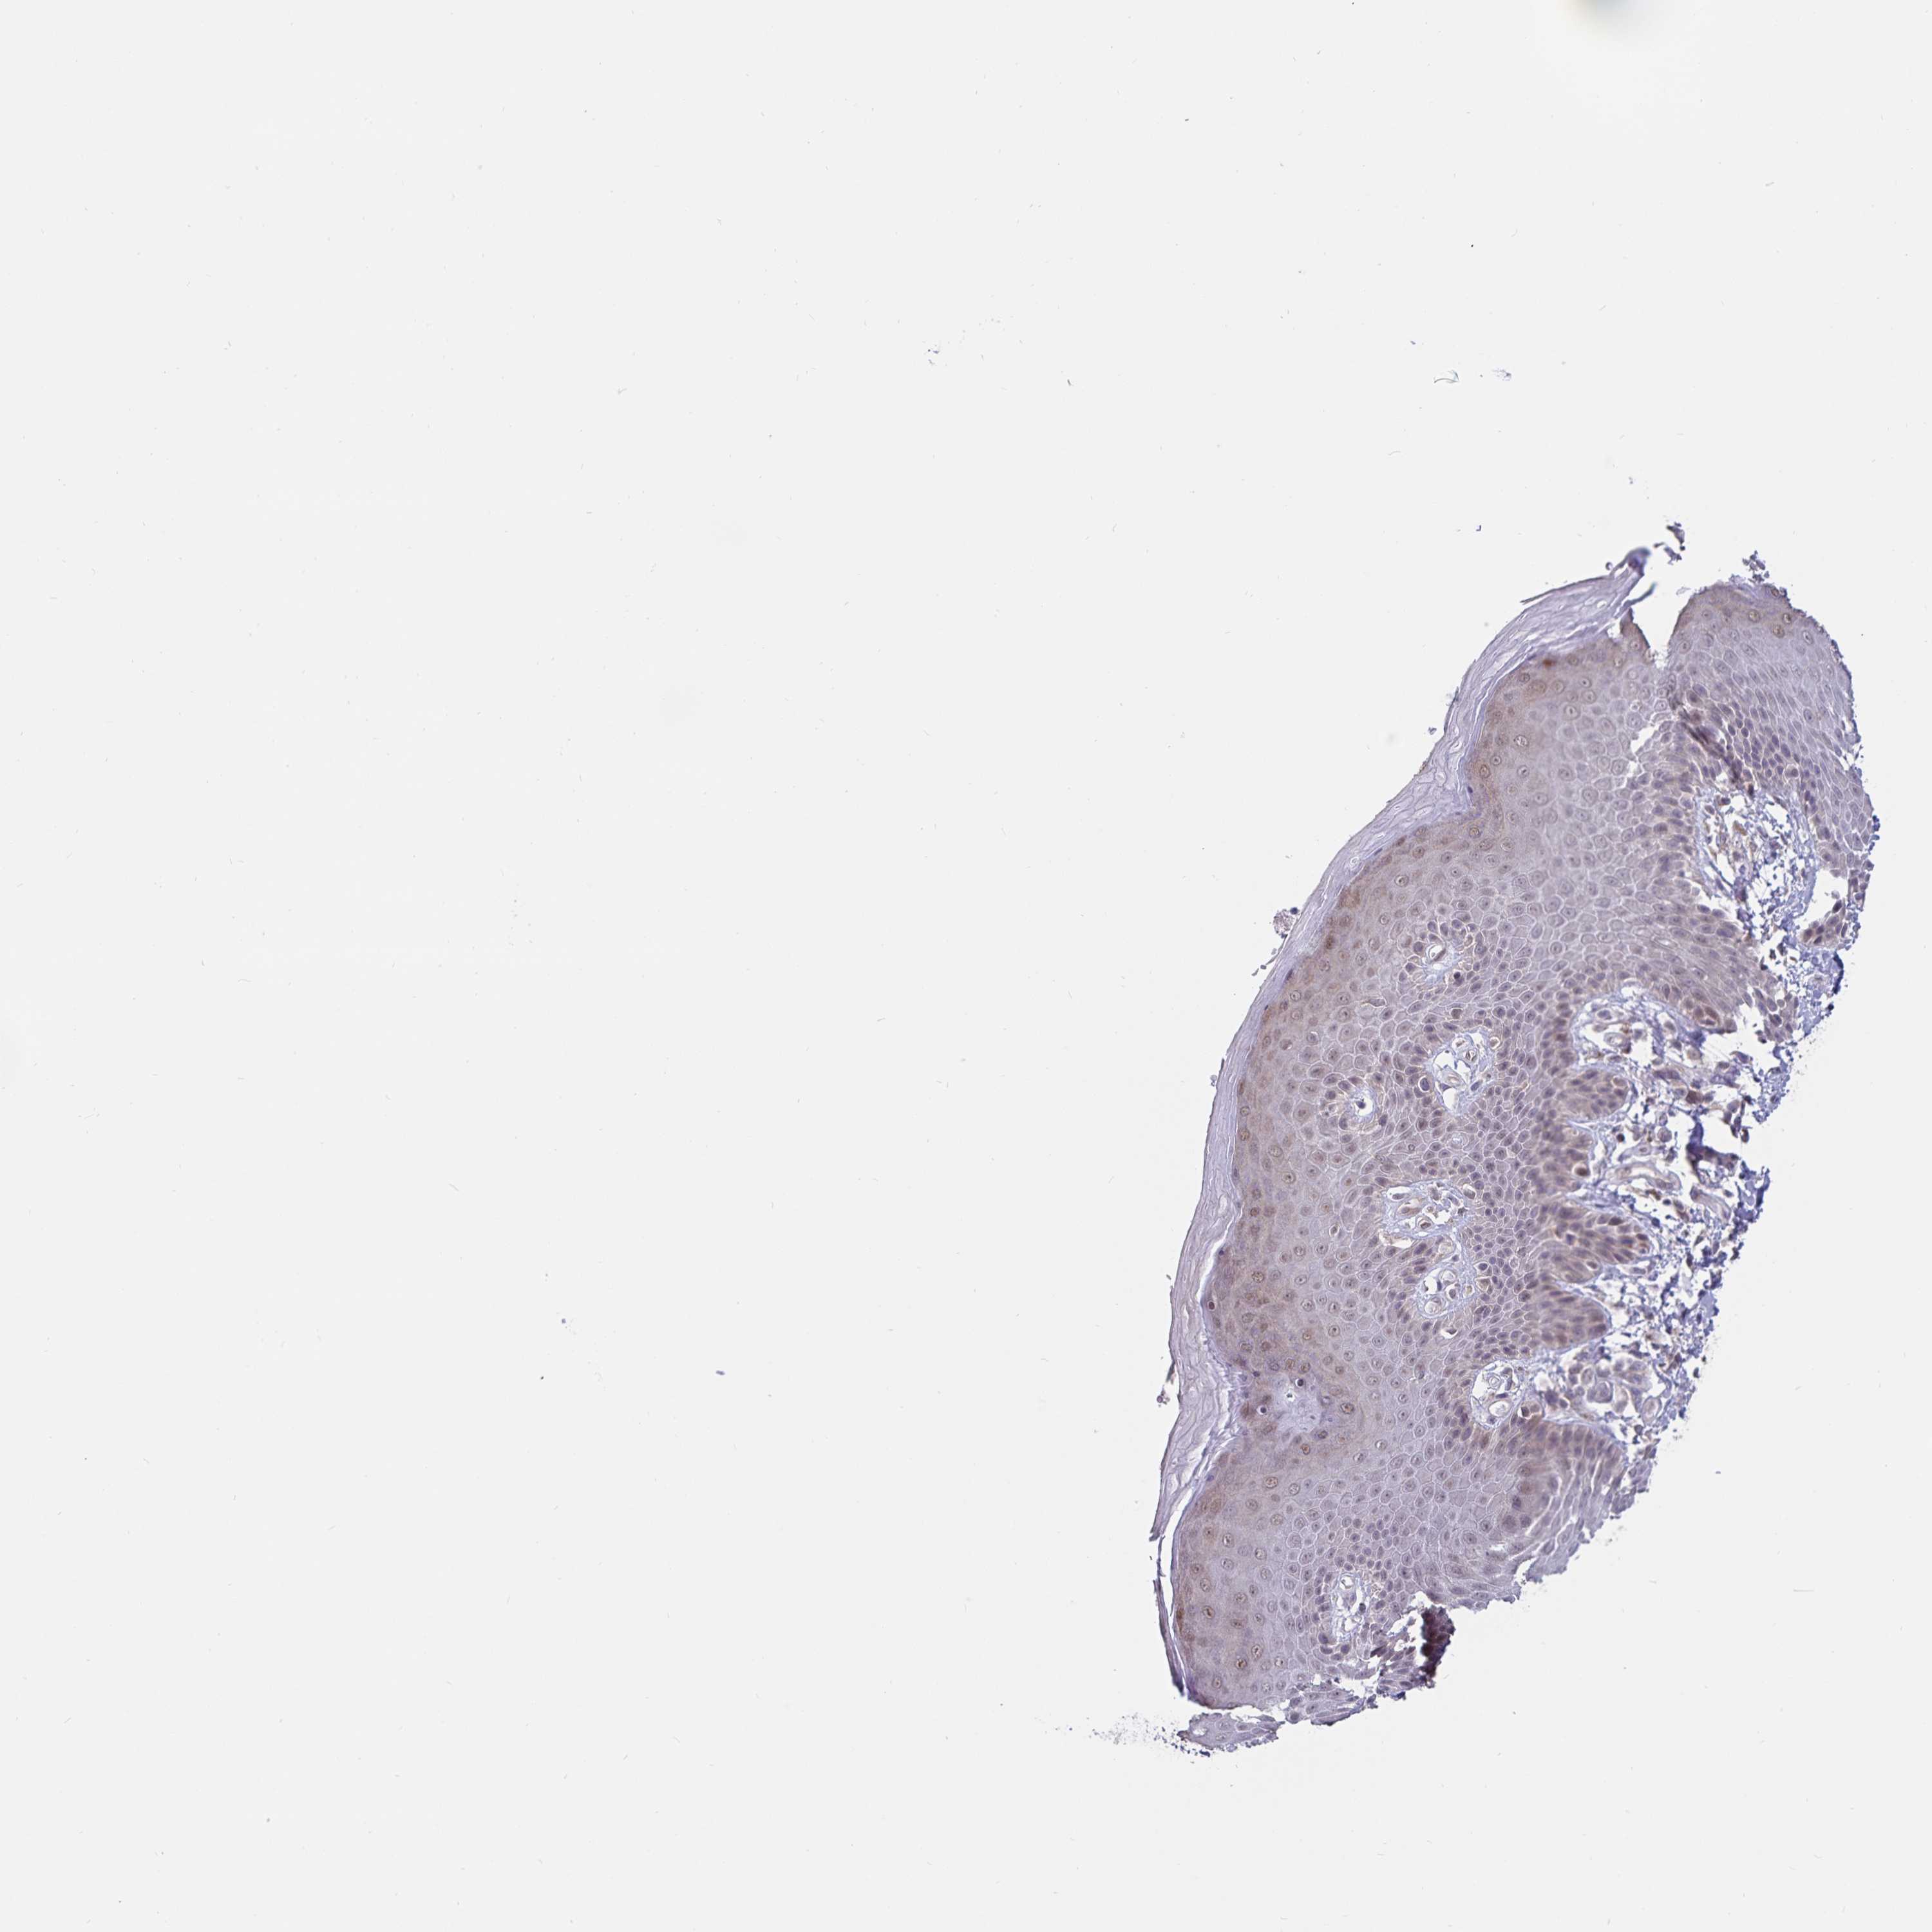

SKIN 1 - Antibody stainingi

Antibody staining in the annotated cell types in the current human tissue is reported as not detected, low, medium, or high, based on conventional immunohistochemistry profiling in selected tissues. This score is based on the combination of the staining intensity and fraction of stained cells.

Each image is clickable and will lead to virtual microscopy that enables deeper exploration of all samples and also displays staining intensity scores, fraction scores and subcellular localization as well as patient and tissue information for each sample.

Antibody HPA062605

Langerhans Not detected

Fibroblasts Not detected

Keratinocytes Not detected

Melanocytes Not detected

SKIN 2 - Antibody stainingi

Epidermal cells Low